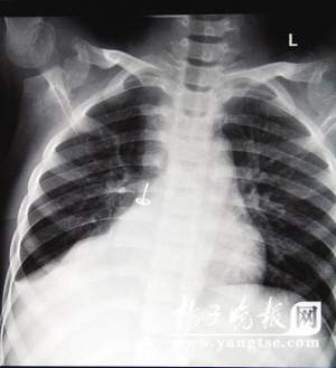

從片子上,圖釘在孩子右肺里“潛伏”得很深,卡在右下葉支氣管。南京市兒童醫(yī)院耳鼻喉科周艾醫(yī)生表示,由于圖釘堵住了孩子支氣管的通道,導(dǎo)致右肺葉不擴(kuò)張,肺部已經(jīng)發(fā)生了實(shí)質(zhì)性的改變,用擴(kuò)張來(lái)進(jìn)行氧氣交換的肺泡都已經(jīng)“癟”下去了,所以孩子的肺部功能非常弱。從片子上看,孩子的右肺已經(jīng)嚴(yán)重“萎縮”,比左肺小了一大圈。